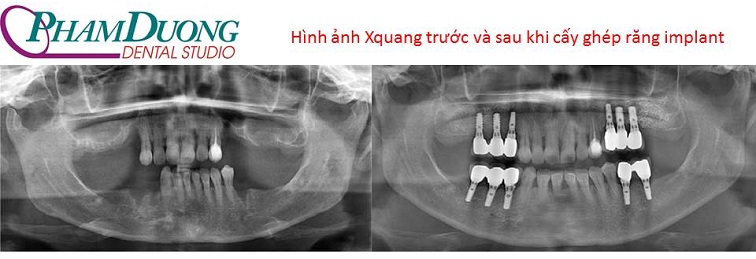

Trường hợp cấy ghép răng implant